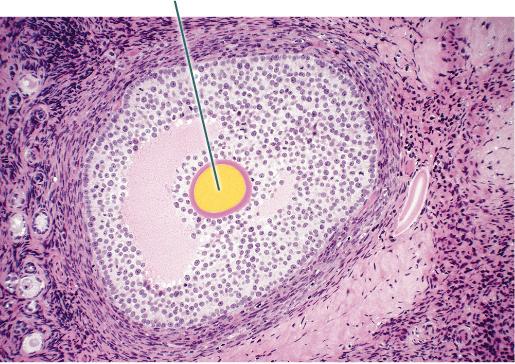

Identify the highlighted structure.

Mature Tertiary Follicle

Identify the highlighted structure.

Oocyte